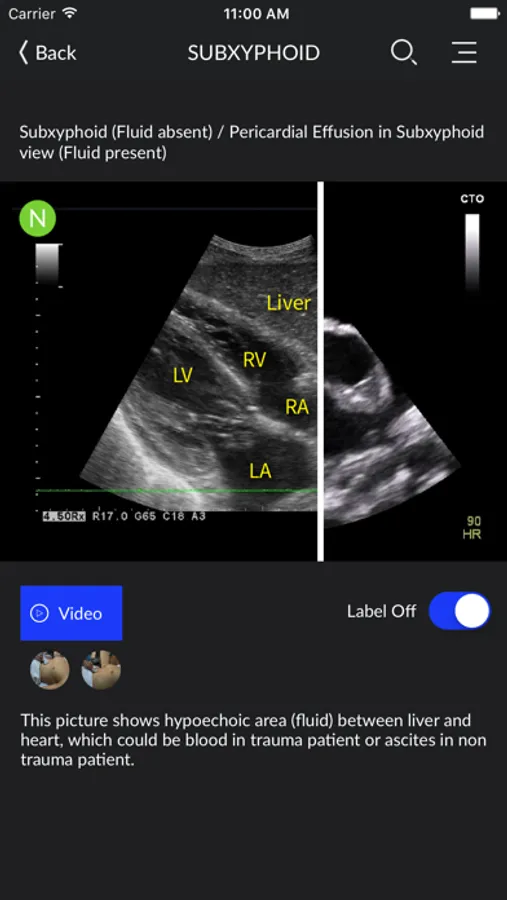

- New swipe function to compare between normal and abnormal images side by side

- Only two categories are available in this version (FAST Exams and IVC) for free download. FAST comes with four sub-categories (Right Upper Quadrant, Left Upper Quadrant, Subxyphoid and Suprapubic)